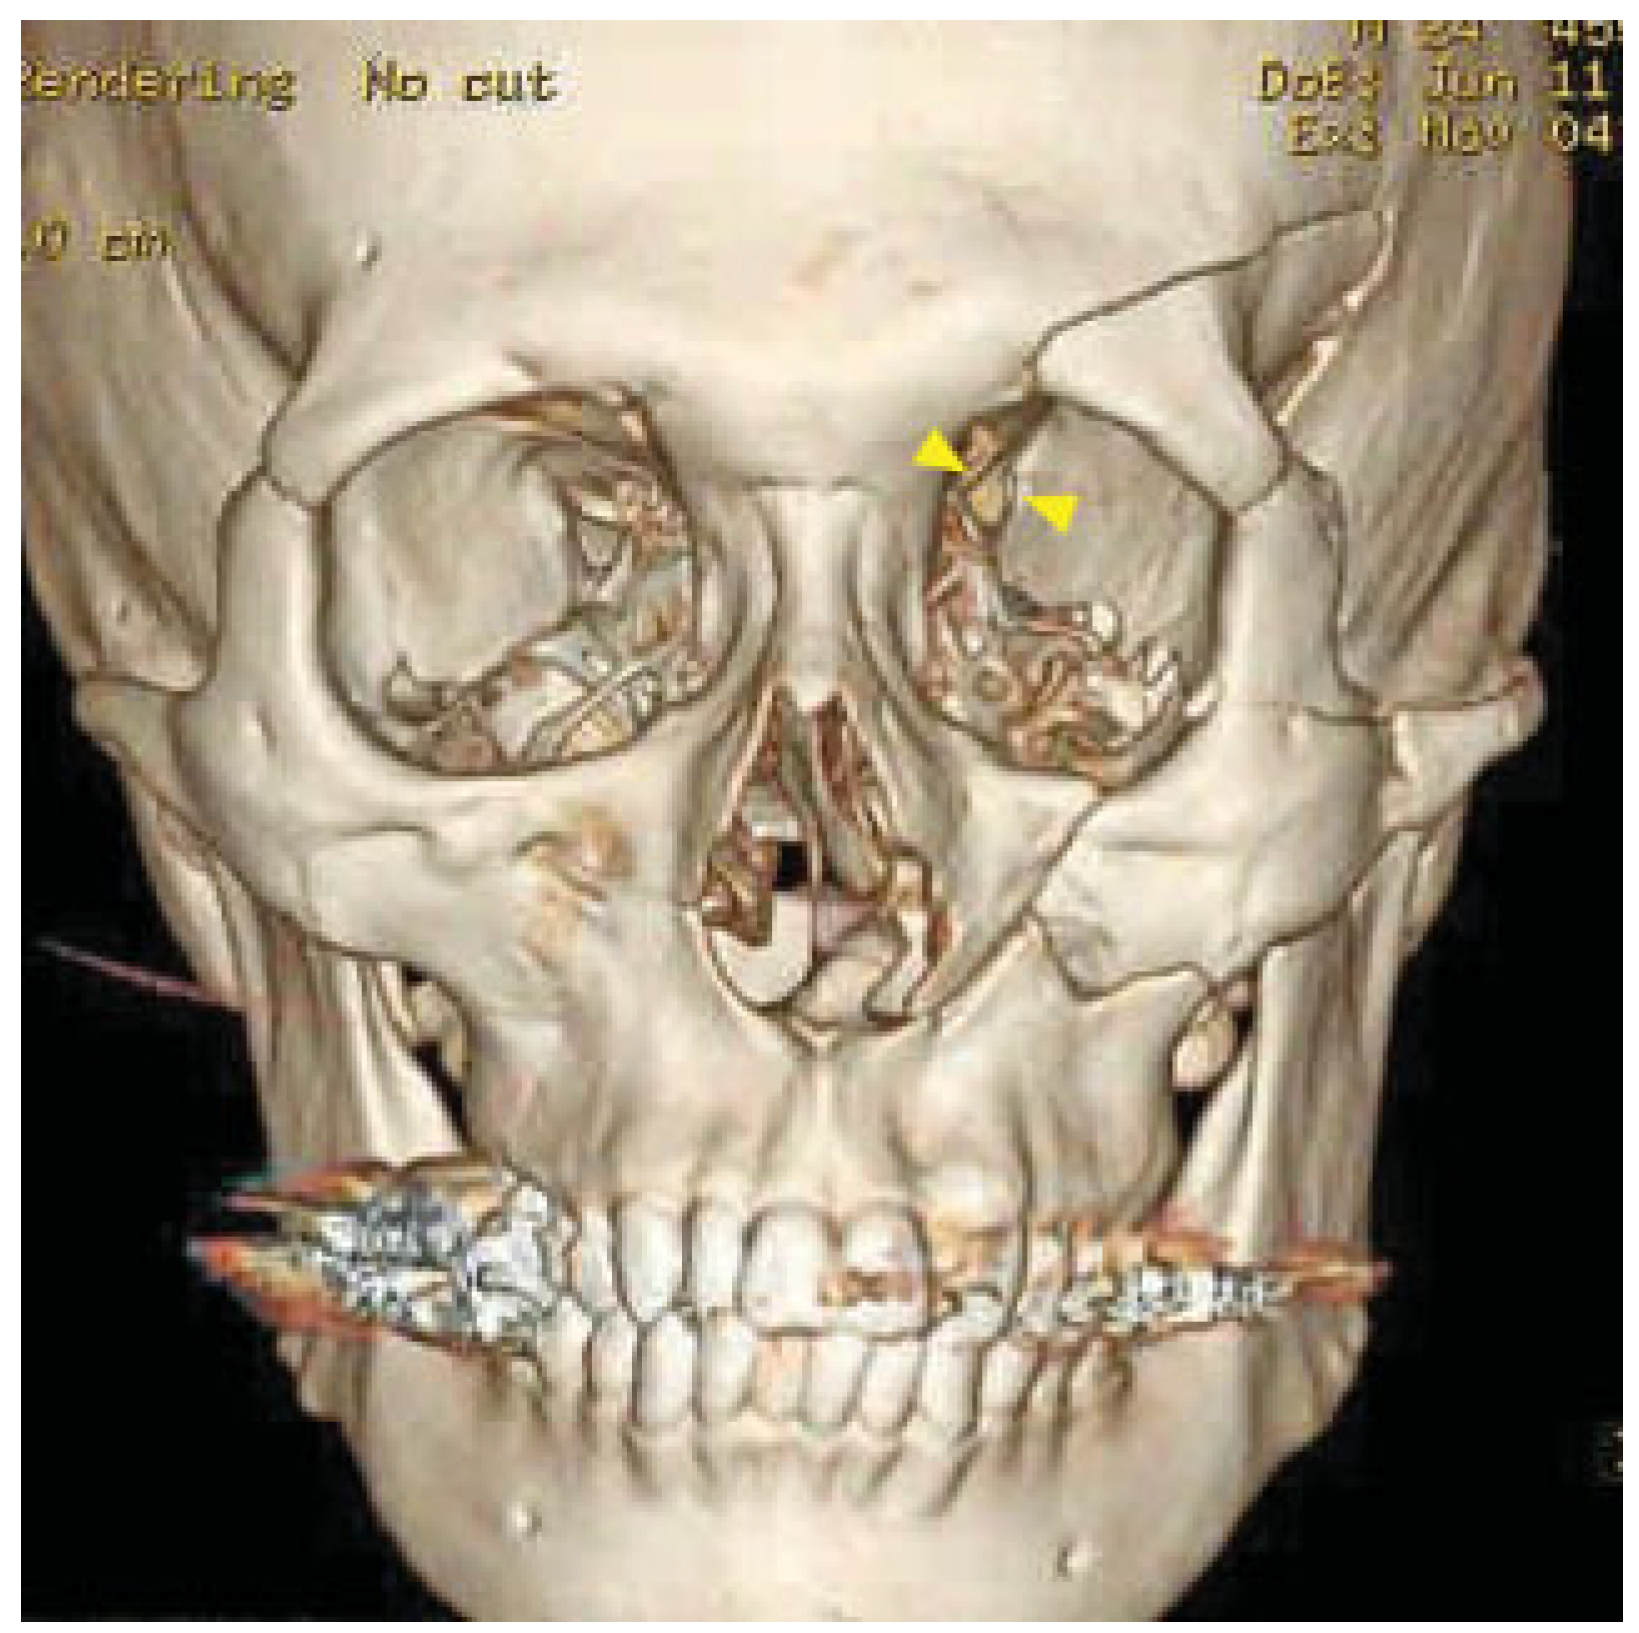

Computed tomography (CT) revealed a left sided orbital and ZMC fracture of the blow-in type, in which the inward displacement of the fractured segments results in decreased orbital volume; there was resultant proptosis of the left eye globe (Figure 2). The superior orbital fissure was compressed by the medially displacement of the fractured segment of the greater wing of the left sphenoid (Figure 3, left). This medially displaced fragment pushed the left anterior clinoid process further medially and caused it also to fracture, which subsequently resulted in optic canal fracture and optic nerve compression (Figure 3, right). A slight left temporal epidural hematoma was also noted. The diagnosis was made of the left blow-in type of orbital and ZMC fracture with associated orbital apex syndrome, due to direct compression of the optic canal and the superior orbital fissure from the displaced fracture fragments.

Figure 2.

Preoperative 3-D CT with blow-in type of orbital and ZMC fracture on left. Narrowed superior orbital fissure (yellow arrowheads) with compression of the medially displaced fracture segment of the greater wing of left sphenoid.